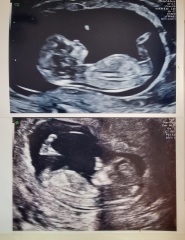

Hi, I am another mum that's had to jump on the nub theory bandwagon. Early Glimpse and Nub Techs have both said boy but The Nub Whisperer has said girl. I will share all images, the last image is of my current pregnancy on top and my son on the bottom just for comparison. I was measuring 12 weeks and 5 days at scan. I have a gender scan in 19 days!!! We can't wait 🥰 please let me know about your experiences with nub theory and what you think of my baby scan ❤️

Homes31 · 05/06/2023 11:07